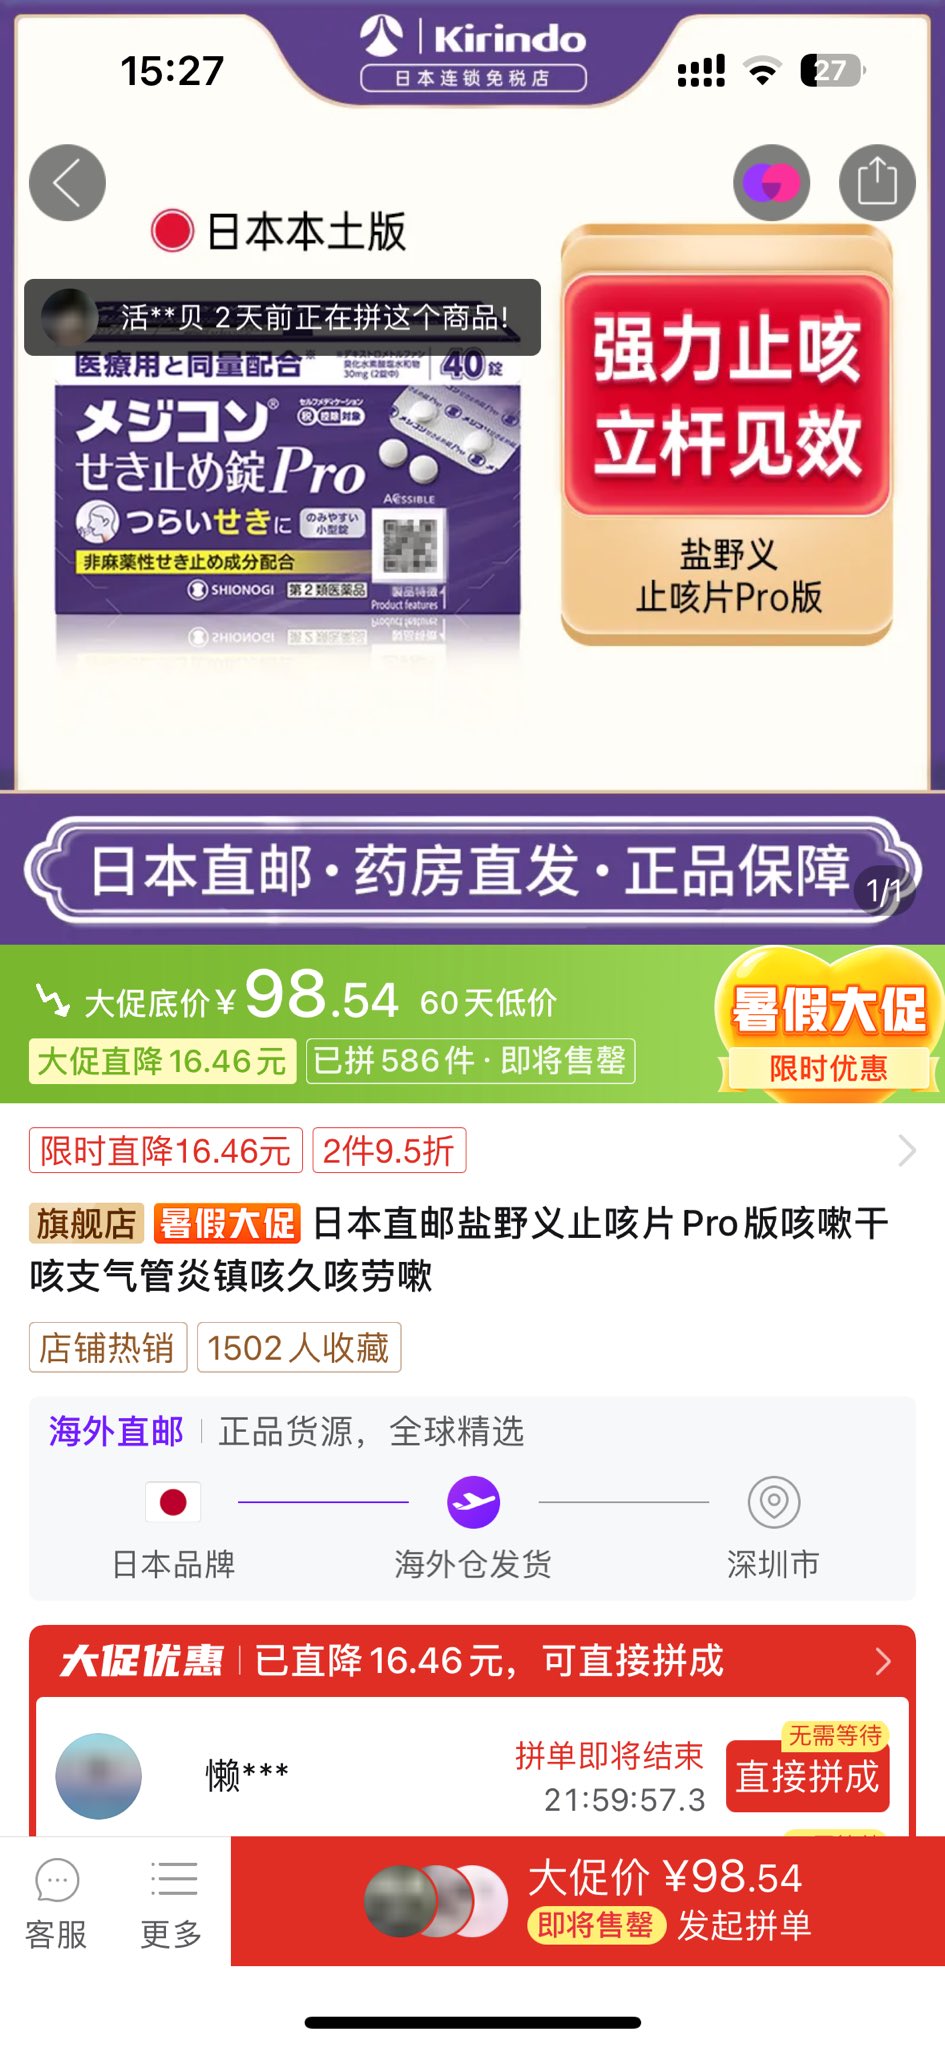

由于我现在快(痛经)痛死了,有感而发简单说说止痛药

常见NSAIDs先稍稍,首选塞来昔布,0.5-1h起效,对肠胃刺激小可以空腹服用,有中上的镇痛强度和中短的持续时间

那么有没有更强的呢🥹有,依托考昔,起效要1h以后,有着22h的长半衰期所以管一整天没什么问题,同样对胃刺激小适合我这种快痛晕过去了直接抓来吃

双氯芬酸钾起效也快适合空腹,但如果胃没那么好就可以一整个分不清哪里在痛了,所以还是垫点食物会比较好

那么再推荐一个双氯芬酸的直肠栓剂版本,直接绕过消化道刺激这关并且起效很快!